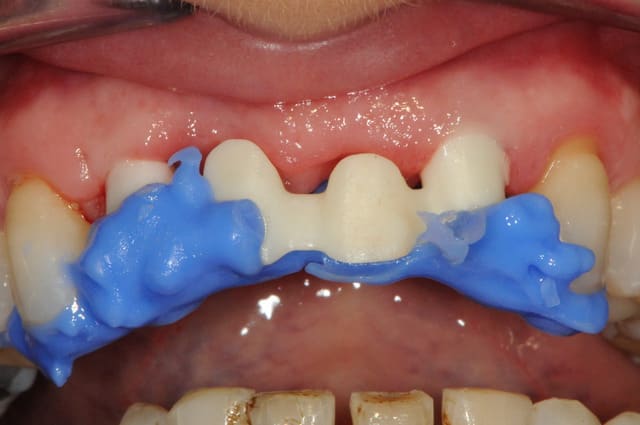

la prothèse immédiate grâce aux empreintes de départ.

ici la résine c'est du protemp 4, c'est super mais un peu gras.